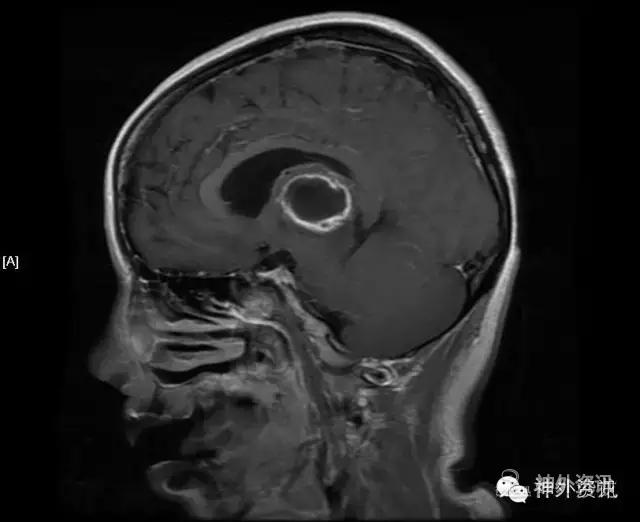

MRI:右侧丘脑占位,考虑胶质瘤可能性大(Ⅲ-Ⅳ级),病灶累及中脑右侧大脑脚,轻度脑积水;不除外转移瘤可能,请结合相关病史及检查。

影像学检查: